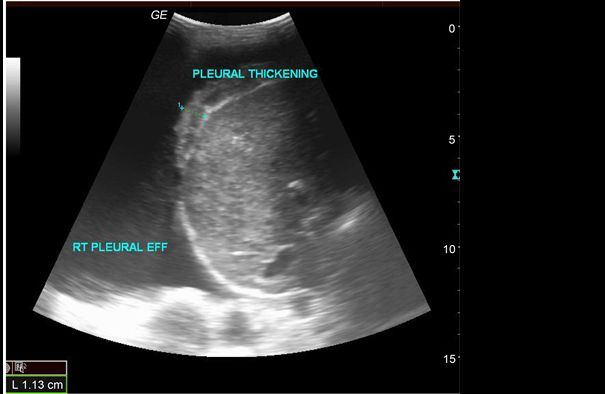

При УЗИ плевральных полостей возможно выявить наличие жидкости, оценить её объём и структуру, опухоли, плевральный фиброз, пневмоторакс, абсцесс, туберкулёзную диссеминацию, наличие сгустков крови в плевральных полостях, возможно также выявить инфаркт лёгкого. Если при обследовании выявлена жидкость или новообразования, то пациенту может быть назначена пункция под контролем УЗИ для определения характера патологического процесса. При ультразвуковом исследовании удаётся изучить более 70% органа, так как возможности ограничиваются анатомическими особенностями плевры.